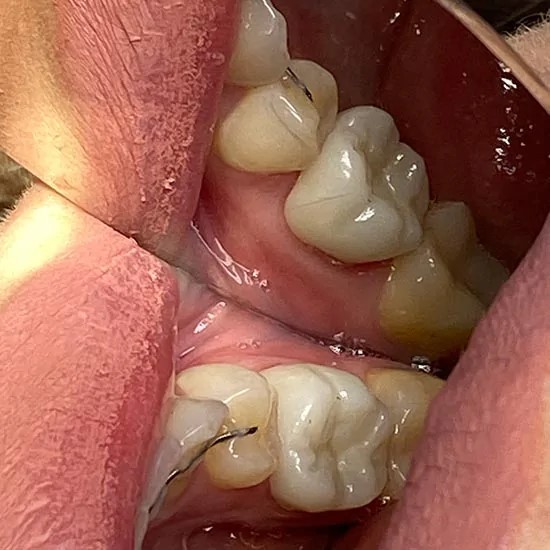

Установка керамической коронки

Также, выполнено протезирование жевательных зубов 16,15,45,47 с компенсацией отсутствующего 46 с помощью керамических коронок E-max с целью восстановления зубного ряда. С помощью коронок заменено положение 15 зуба в дуге, восстановлена анатомическая форма 16, замещен включенный дефект в области 46, восстановлена жевательная эффективность.

Доктор: Баташов Алексей Олегович